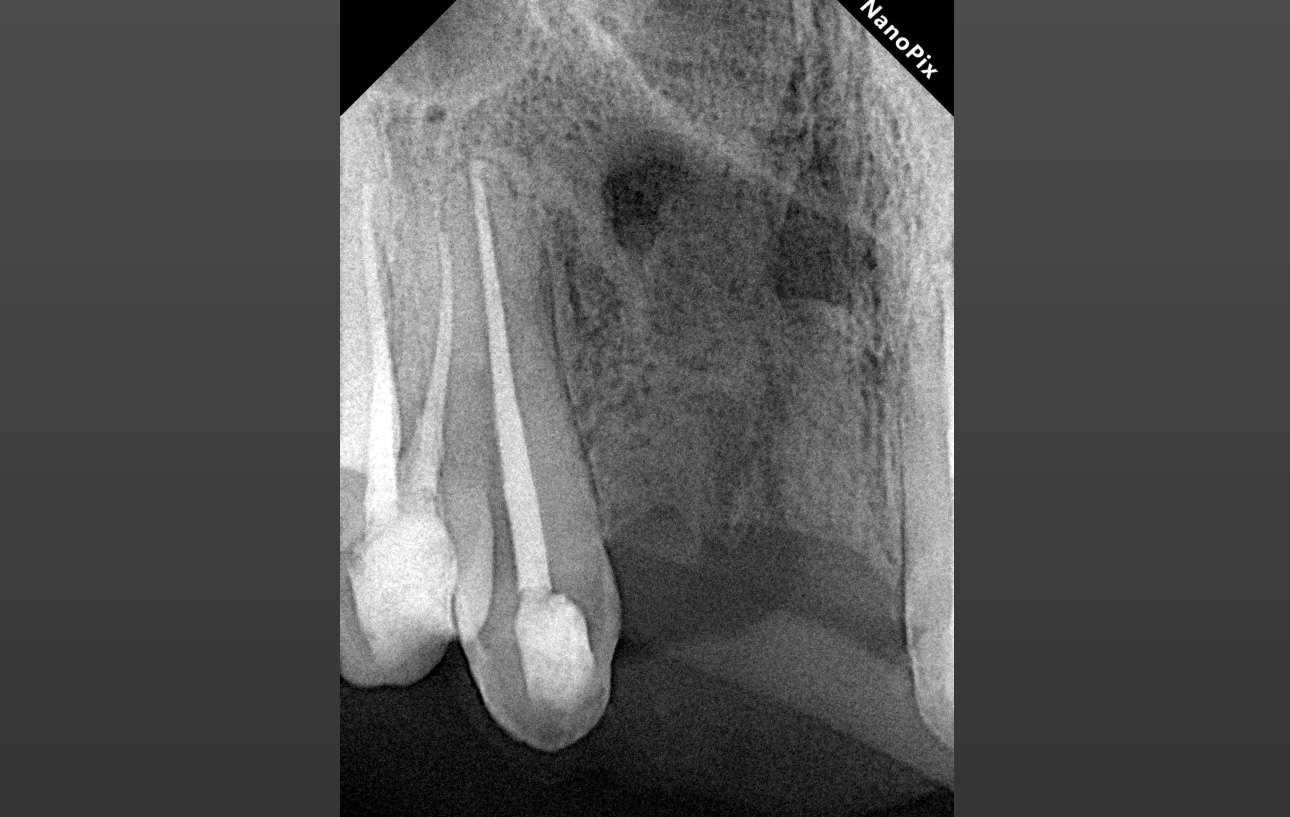

1.3 Хронический апикальный периодонтит.

Длина корневого канала 24 мм.

Обтурация биокерамическим силером с гуттаперчей. Автор: Диана Кипарисова